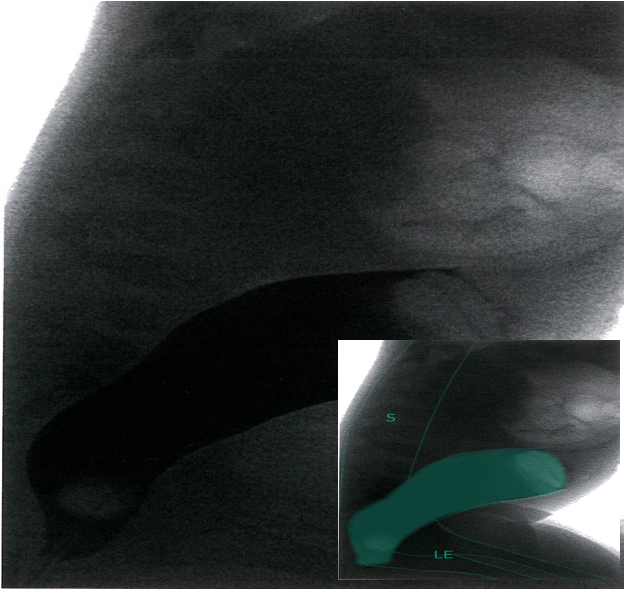

Contrast enema; lateral view

Rectum and lower sigmoid are filled with contrast (dark); sudden interruption of contrast in the upper sigmoid (green area).

- S = spine

- LE = lower extremity